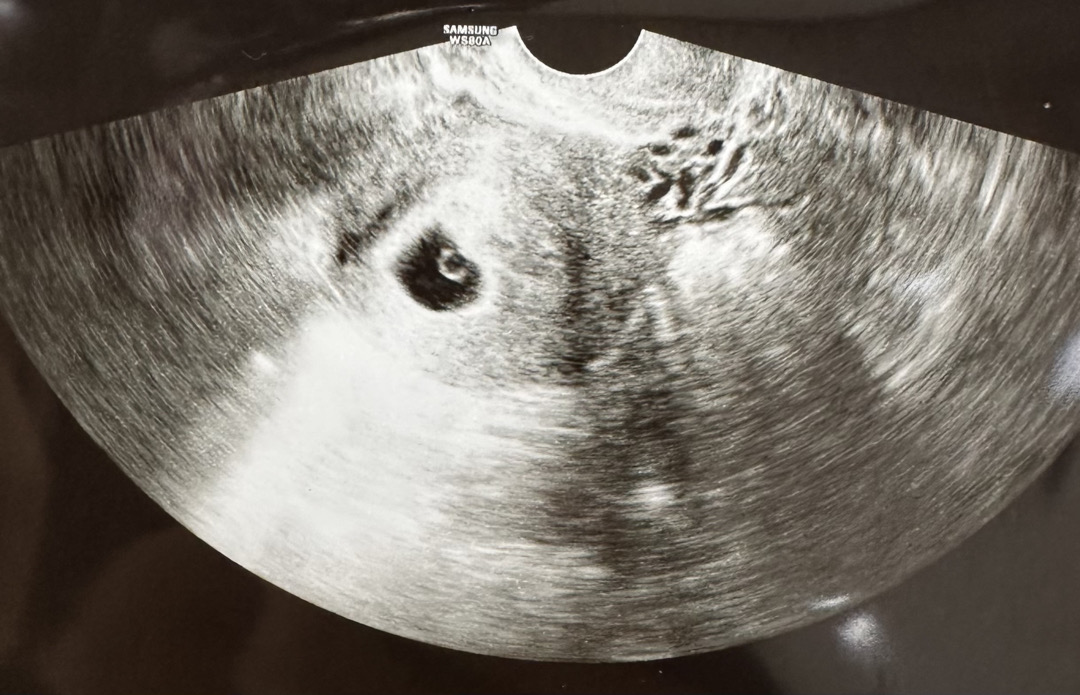

난황까지 보고왔어요!

오늘이 마지막 생리일 기준 5주 0일차인데 아기집에 난황까지 잘 보이더라구요..! 다음주면 심장소리 들을 수 있을 것 같다고 하셨어요🤍 아기집만 잘 보이면 좋겠다 싶었는데 난황까지 보니 제가 임신한게 조금씩 실감나는 것 같아요 ㅎㅎ 얼른 다음주 되면 좋겠어요